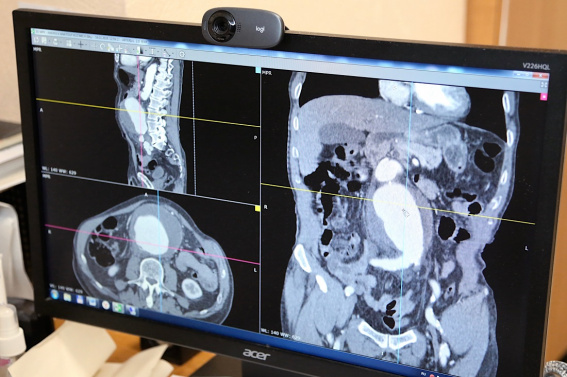

Житель Боровичского округа поступил в центральную районную больницу с жалобами на боль в животе. При обследовании была выявлена аневризма брюшного отдела аорты диаметром 10 см, что в пять раз превышает нормальный размер. Состояние осложнилось разрывом стенки сосуда.

Операцию выполнила бригада специалистов Новгородской областной клинической больницы. Разорвавшуюся аневризму удалили, а повреждённый участок сосуда заменили специальным синтетическим протезом. Сейчас пациент чувствует себя хорошо и в ближайшее время выпишется из больницы под диспансерное наблюдение в поликлинике по месту жительства.